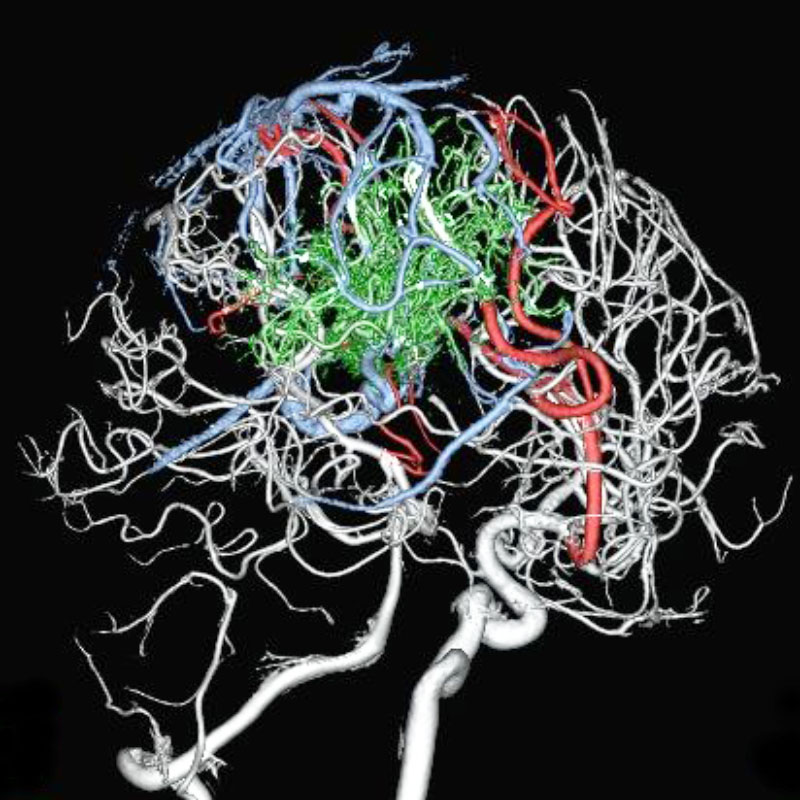

脳動静脈奇形

血管塞栓術

松田/濵田/元永